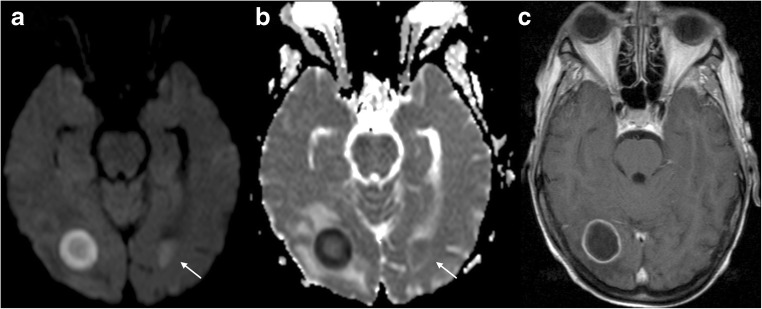

Another use of DWI on imaging of CNS tumours is to aid in the distinction between glioblastoma and primary CNS lymphoma, two entities with markedly different treatment strategies and not always easy to differentiate with conventional imaging in patients presenting with an enhancing brain mass. Due to its higher cellularity compared with GBM, primary CNS lymphoma has been shown to exhibit lower ADC values [39]. There are some published works aiming to find an ADC threshold for differentiating lymphoma from other tumours [40] (Fig. 5). Guzman et al. reported higher ADC values in the more aggressive tumours (comparing glioblastoma and metastasis vs. low-grade glioma) [41].

Fig. 5.

Primary CNS lymphoma. Left frontal periventricular lesion showing prominent diffusion restriction, presenting with hyperintensity on DWI (a), low ADC value (b) and mild hyperintensity on T2WI (c), all typical features of this type of hypercellular tumour. T1WI post gadolinium (d) shows homogeneous and intense contrast enhancement